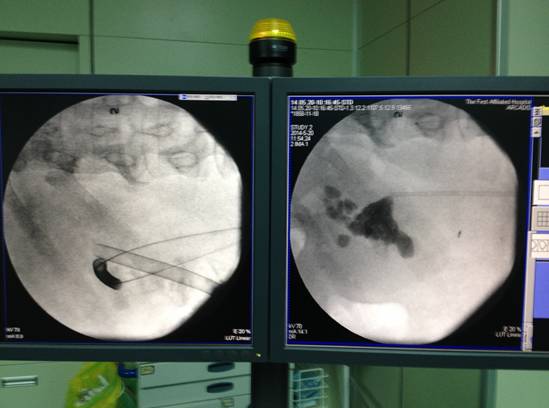

C臂X线下通过输尿管导管逆行打入造影剂,肾盂肾盏显影(黑色显影的部分),穿刺定位选择合适目标。

C臂X线定位下选择合适的目标肾脏进行穿刺建立通道。

激情过后,这个时候就要打扫战场了,通过术中C臂X线透视,我们可以看到是否还有残留的结石,把漏网之鱼一网打尽后,接下来做好安全措施,放置肾造瘘管、输尿管支架管,手术顺利完成!

上图右边是手术前的结石显影(黑色的就是结石),左边是建立的两个通道手术结束后确认结石已经全部清除干净(原来黑色的部分全部消失),只留下两个工作鞘和导丝。